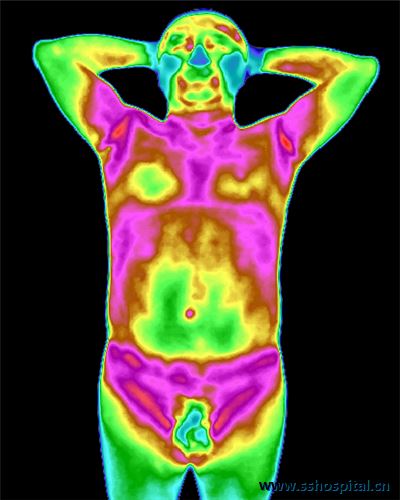

无明显不适,但检查出胃肠病变!红外热成像技术了解一下

红外热成像技术作为诊断和治疗的一种评估方法,已广泛用于医学领域。 案     例 近期,年过六旬的光叔,因痛风来三水区人民医院中医科就诊,一次红外热成像检查中发现其上腹部低温改变,***虑胃肠存...